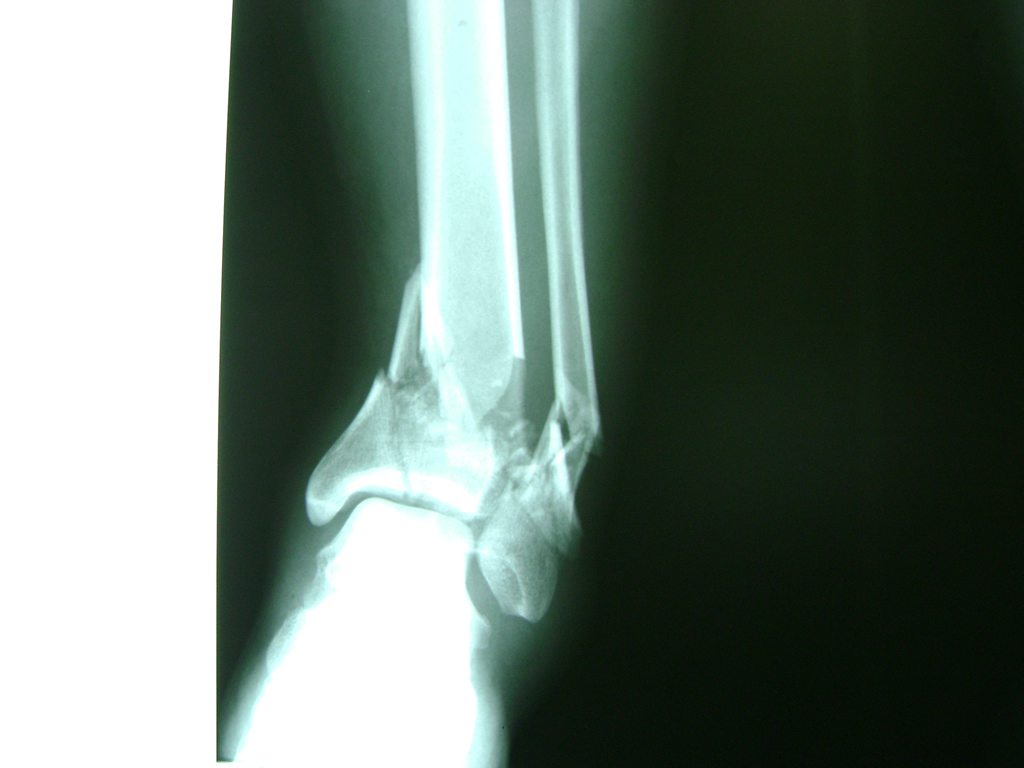

Una fractura de tobillo es la rotura de uno o más de los huesos del tobillo. Estas fracturas pueden ser:

Algunas fracturas de tobillo pueden requerir cirugía si:

- Los extremos de los huesos están desalineados entre sí (desplazados).

- La fractura se extiende hasta la articulación del tobillo (fractura intra-articular).

Cuando se necesita cirugía, es probable que esta implique el uso de clavijas de metal, tornillos o placas para sostener los huesos en su lugar mientras la fractura se consolida. Los elementos de soporte pueden ser temporales o permanentes.